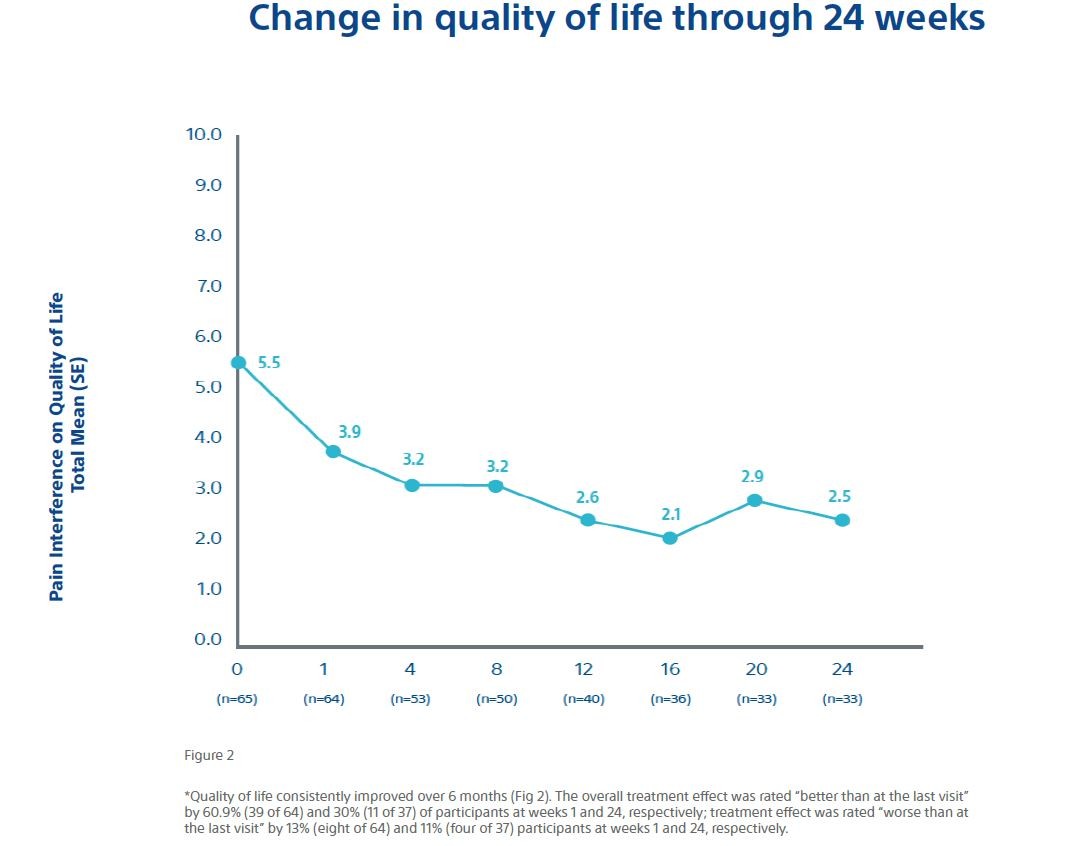

Separate evaluations of ancillary efficacy endpoints were also made through 24 weeks, including: (a) changes in worst pain scores and average pain scores from baseline; (b) change in analgesic use (both morphine equivalent daily dose (MEDD) and nonsteroidal anti-inflammatory drugs); (c) use of additional therapies for persistent or recurrent pain associated with the index tumor or new metastases; (d) quality of life (as indicated by change from baseline in overall average BPI-SF); and (e) change in Karnofsky performance status as a measure of functional impairment. The safety endpoint was the incidence and severity of procedure or device-related adverse events.

- Quality of life improved over the course of the study period.

Overall, the data shows a rapid and durable pain relief along with a decrease in MEDD and a corresponding increase in the quality of life for patients with bone metastases.